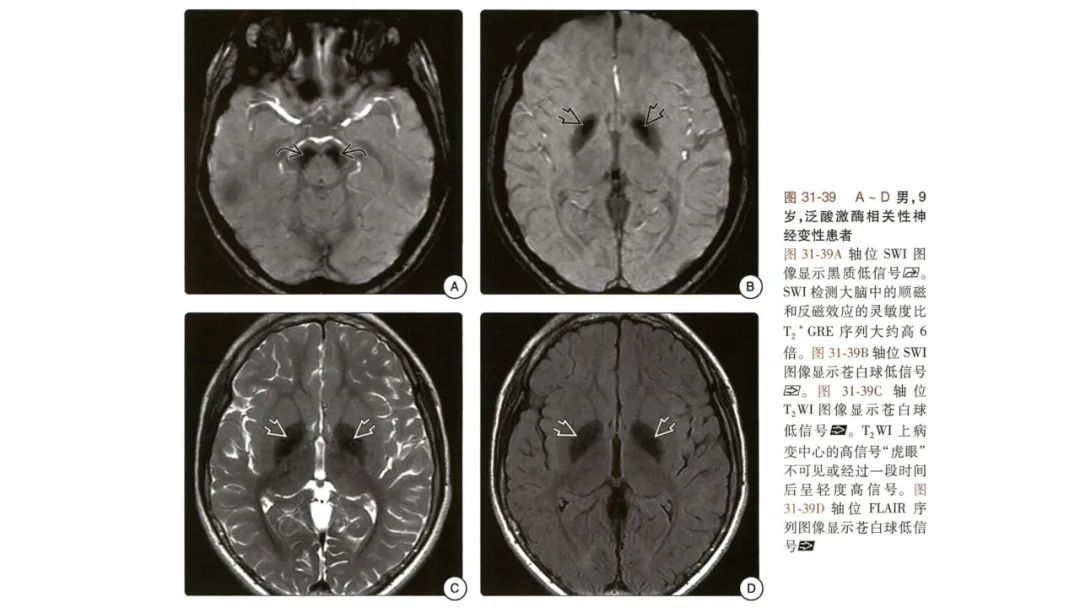

颅脑影像诊断基础知识讲座:主要累及灰质的遗传性代谢性疾病